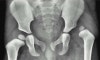

X-ray : 선천성 고관절 탈구(Congenital Hip Dislocation)